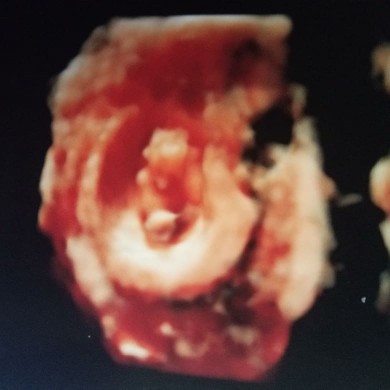

USG 4D

3D aja uda jels bun, 95+2d

Itu usg 4d, kalo usg 2d harga 175.000